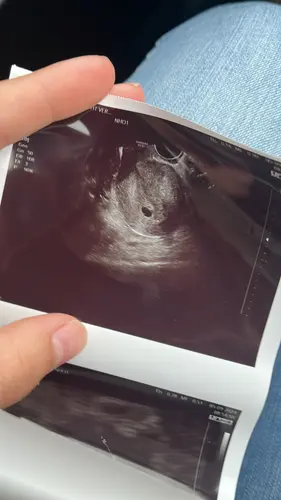

Heel gaaf! Was je precies 6 weken? Ik heb met 6+1 of 6+2 een eerste echo (medisch), maar vraag me af of het hartje dan al kan kloppen. Las online 6e week, maja welke dag in de 6e week denk ik dan haha

Ik lees bijna overal dat dit vanaf 5+3/4 een beetje gebeurt en afhankelijk van hoe goed ze kunnen zien, zou je rond de 6 weken wel een beetje wat moeten kunnen zien ♡